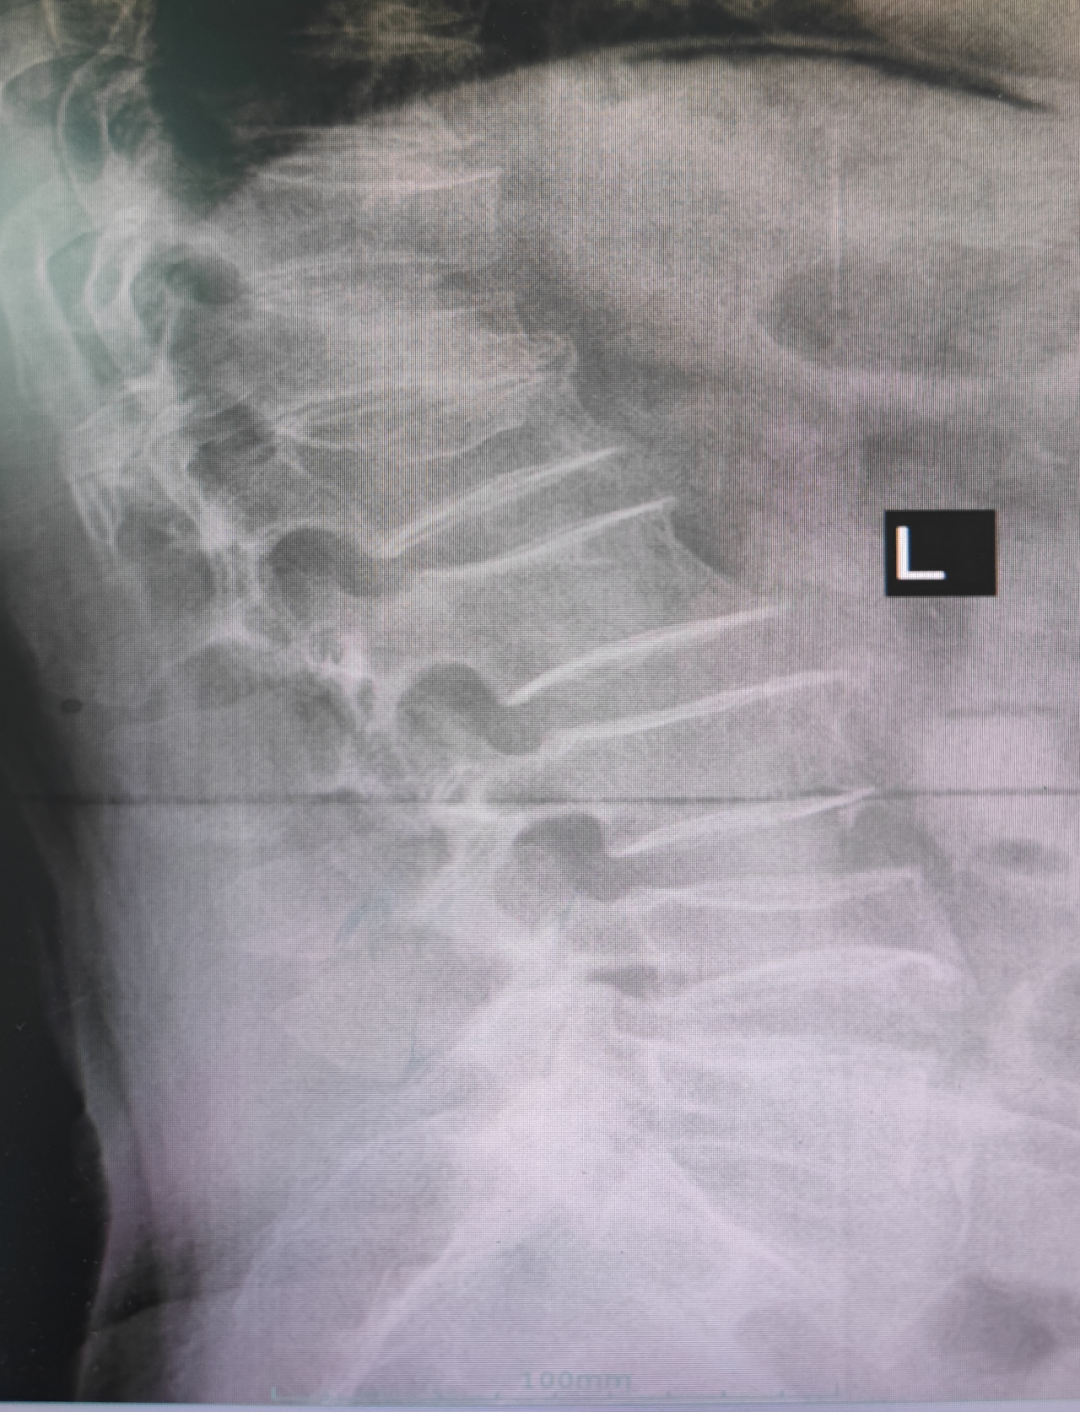

病例回顧 骨折部位 術(shù)中C臂協(xié)助定位 在C-臂監(jiān)視器透視下,分別定位胸12雙側(cè)椎弓根位置,標記穿刺點,僅以穿刺點為中心做3mm切開,在透視下注入骨水泥,再次透視見骨水泥位置良好。 骨水泥注入 術(shù)后影像學檢查 手術(shù)切口1cm左右 該手術(shù)經(jīng)皮透視下穿刺,手術(shù)切口小,創(chuàng)傷小,無需縫合,術(shù)后患者即感腰部疼痛明顯減輕,第二天可下床行走,已無腰痛不適,張大娘非常高興,自己再也不會受腰痛折磨整日與床為伴了。 我院脊柱骨科近年來,已成功開展多臺PVP手術(shù),為廣大老年患者減輕了病痛,減少了患者臥床時間,提高了生活質(zhì)量,是骨質(zhì)疏松性椎體骨折患者的福音。如果家里的老人突然出現(xiàn)了腰背疼痛,翻身下床困難,或者出現(xiàn)了腹部不適,排除腹部疾病(因為很多胸腰椎骨折患者在早期以腹痛腹脹為最主要癥狀),無論有沒有外傷史,建議帶老人及早就醫(yī),如果發(fā)現(xiàn)椎體損傷,積極治療,讓老人度過一個輕松愉快的晚年生活。 科普小講堂:經(jīng)皮椎體成形術(shù) 什么是骨質(zhì)疏松性椎體骨折? 骨質(zhì)疏松性椎體壓縮骨折,即在日常生活中患者并未遭受到明顯的外力而發(fā)生的骨折。這種骨折與創(chuàng)傷性的骨折不同,是由于自身骨質(zhì)疏松所導(dǎo)致的骨組織病變。骨質(zhì)疏松性骨折發(fā)生時,患者會感覺到背部明顯疼痛,翻身或起床等動作會讓疼痛更加明顯。 骨質(zhì)疏松性椎體壓縮骨折的危害有哪些? 一旦椎體發(fā)生骨質(zhì)疏松性椎體壓縮骨折,常常會導(dǎo)致患者出現(xiàn)腰背部持續(xù)性疼痛、季肋部放射痛、后凸畸形、呼吸功能受限及胃腸道癥狀等諸多癥狀,造成老年患者生活質(zhì)量下降。 什么是經(jīng)皮椎體成形術(shù)? (Percutaneousvertebroplasty,PVP)是一種新型的脊柱微創(chuàng)手術(shù),通過采用經(jīng)皮穿刺的方法,經(jīng)過椎弓根或是直接向椎體中注入骨水泥,使得椎體的強度和穩(wěn)定性得以提升,防止塌陷,從而達到緩解腰背疼痛,甚至部分恢復(fù)椎體高度的目的。 PVP手術(shù)優(yōu)點是什么? 1.恢復(fù)顯著:通常術(shù)后6個小時即能達到穩(wěn)定固定,患者可下床站立活動,大大縮短了患者臥床的時間。 2.疼痛減輕:術(shù)后患者會發(fā)現(xiàn)腰背部疼痛明顯減輕。 3.微創(chuàng):該治療方法僅需在皮膚上留2-3mm的穿刺針孔。 4.安全性:由于手術(shù)采用的是局部麻醉,因此即便是存在多種基礎(chǔ)病的患者也能夠耐受手術(shù),整個手術(shù)過程相對安全。 就診地址 酒泉市中醫(yī)醫(yī)院四樓脊柱骨科 咨詢電話 一樓門診部:0937-2669161 王醫(yī)生:13209409826 ??? 張醫(yī)生:18219971722